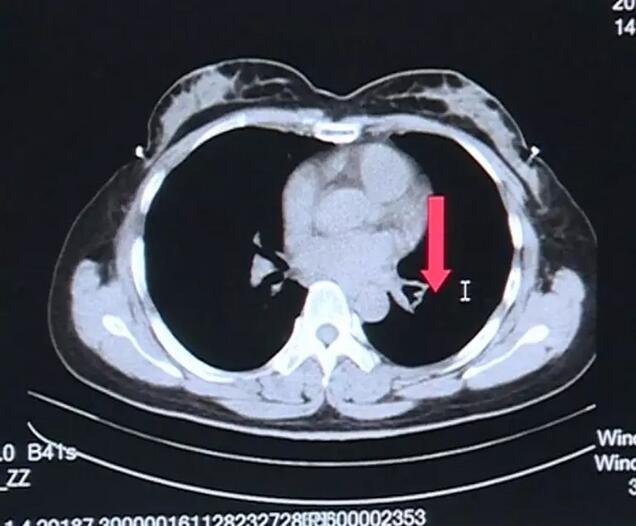

易女士在左下肺部有一個(gè)大的腫塊,我們經(jīng)過一個(gè)多月的放療之后,前兩天復(fù)查了CT ,復(fù)查之后,原來在左下肺的病灶 ,現(xiàn)在就完全不見了。